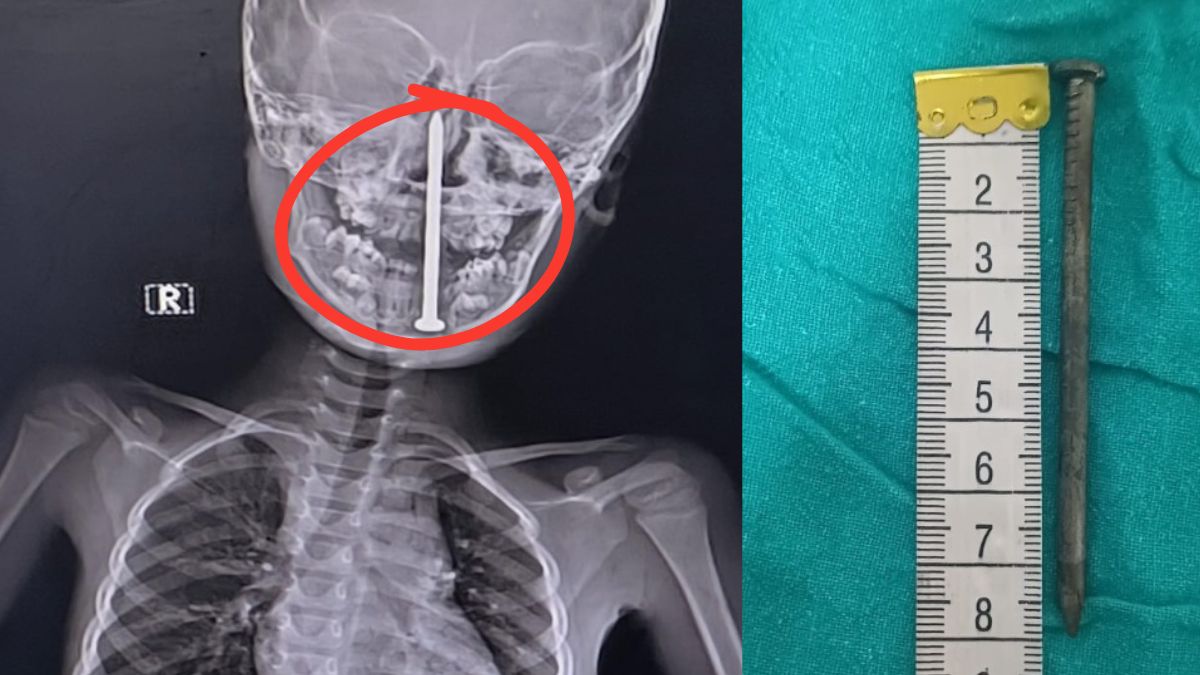

हाल ही में किंग जॉर्ज मेडिकल यूनिवर्सिटी (KGMU) में ऐसा ही एक चौंकाने वाला मामला सामने आया। बलरामपुर के नवाजपुर गांव के 7 साल के बच्चे के सिर में गर्दन के रास्ते एक 8 सेंटीमीटर लंबी कील घुस गई थी। बच्चा खेलते वक्त गिर गया और कील सीधे दिमाग तक जा पहुंची। पहले उसे बलरामपुर के निजी अस्पताल ले जाया गया, फिर KGMU में 10 घंटे लंबा ऑपरेशन कर बच्चे की जान बचाई गई। ऐसे में जरूरी है कि आप जानें कि इस स्थिति में तुरंत क्या करना चाहिए और क्या नहीं?

अगर बच्चा सिक्का या कील जैसी ठोस चीज निगल ले, तो ये तभी खतरनाक होता है जब वो श्वास नली (फेफड़ों के रास्ते) में चला जाए। यह तुरंत दम घुटने का कारण बन सकता है। ऐसे मामलों में डॉक्टर एक्स-रे करके पता लगाते हैं कि वह वस्तु कहां फंसी है, पेट में, आंतों में या फेफड़ों में। ज़रूरत पड़ने पर पेडियाट्रिक सर्जन से ऑपरेशन भी कराया जाता है।